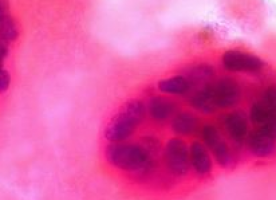

Two Johns Hopkins engineers say they have found an easy way to use gravity or simple forces to similarly sort microscopic particles and bits of biological matter -- including circulating tumour cells.

"The ultimate goal is to develop a simple device that can be used in routine checkups by health care providers," said doctoral student Bernate, who is lead author on the paper. "It could be used to detect the handful of circulating tumor cells that have managed to survive among billions of normal blood cells. This could save millions of lives."

Ideally, these cancer cells in the bloodstream could be detected and targeted for treatment before they've had a chance to metastasize, or spread cancer elsewhere. Detection at early stages of cancer is critical for successful treatment.